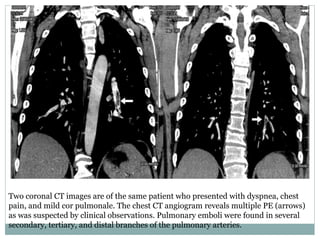

Two coronal CT images are of the same patient who presented with dyspnea, chest

pain, and mild cor pulmonale. The chest CT angiogram reveals multiple PE (arrows)

as was suspected by clinical observations. Pulmonary emboli were found in several

secondary, tertiary, and distal branches of the pulmonary arteries.